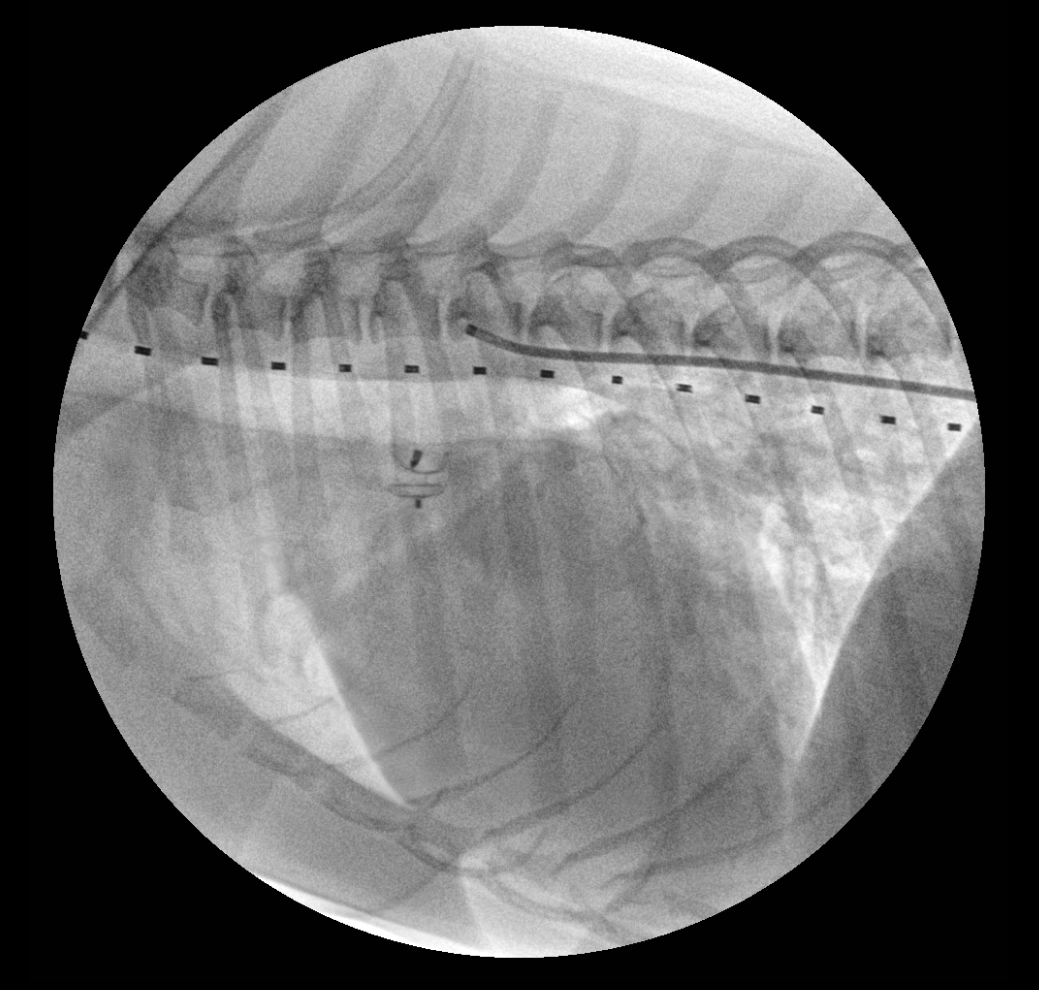

PDA 교정 시술 투시 영상

시술 투시 영상 1

C-arm을 이용한 실시간 투시 영상 가이드 하에 카테터 삽입 과정

시술 투시 영상 2

정확한 위치에 PDA plug 삽입하는 과정의 투시 영상